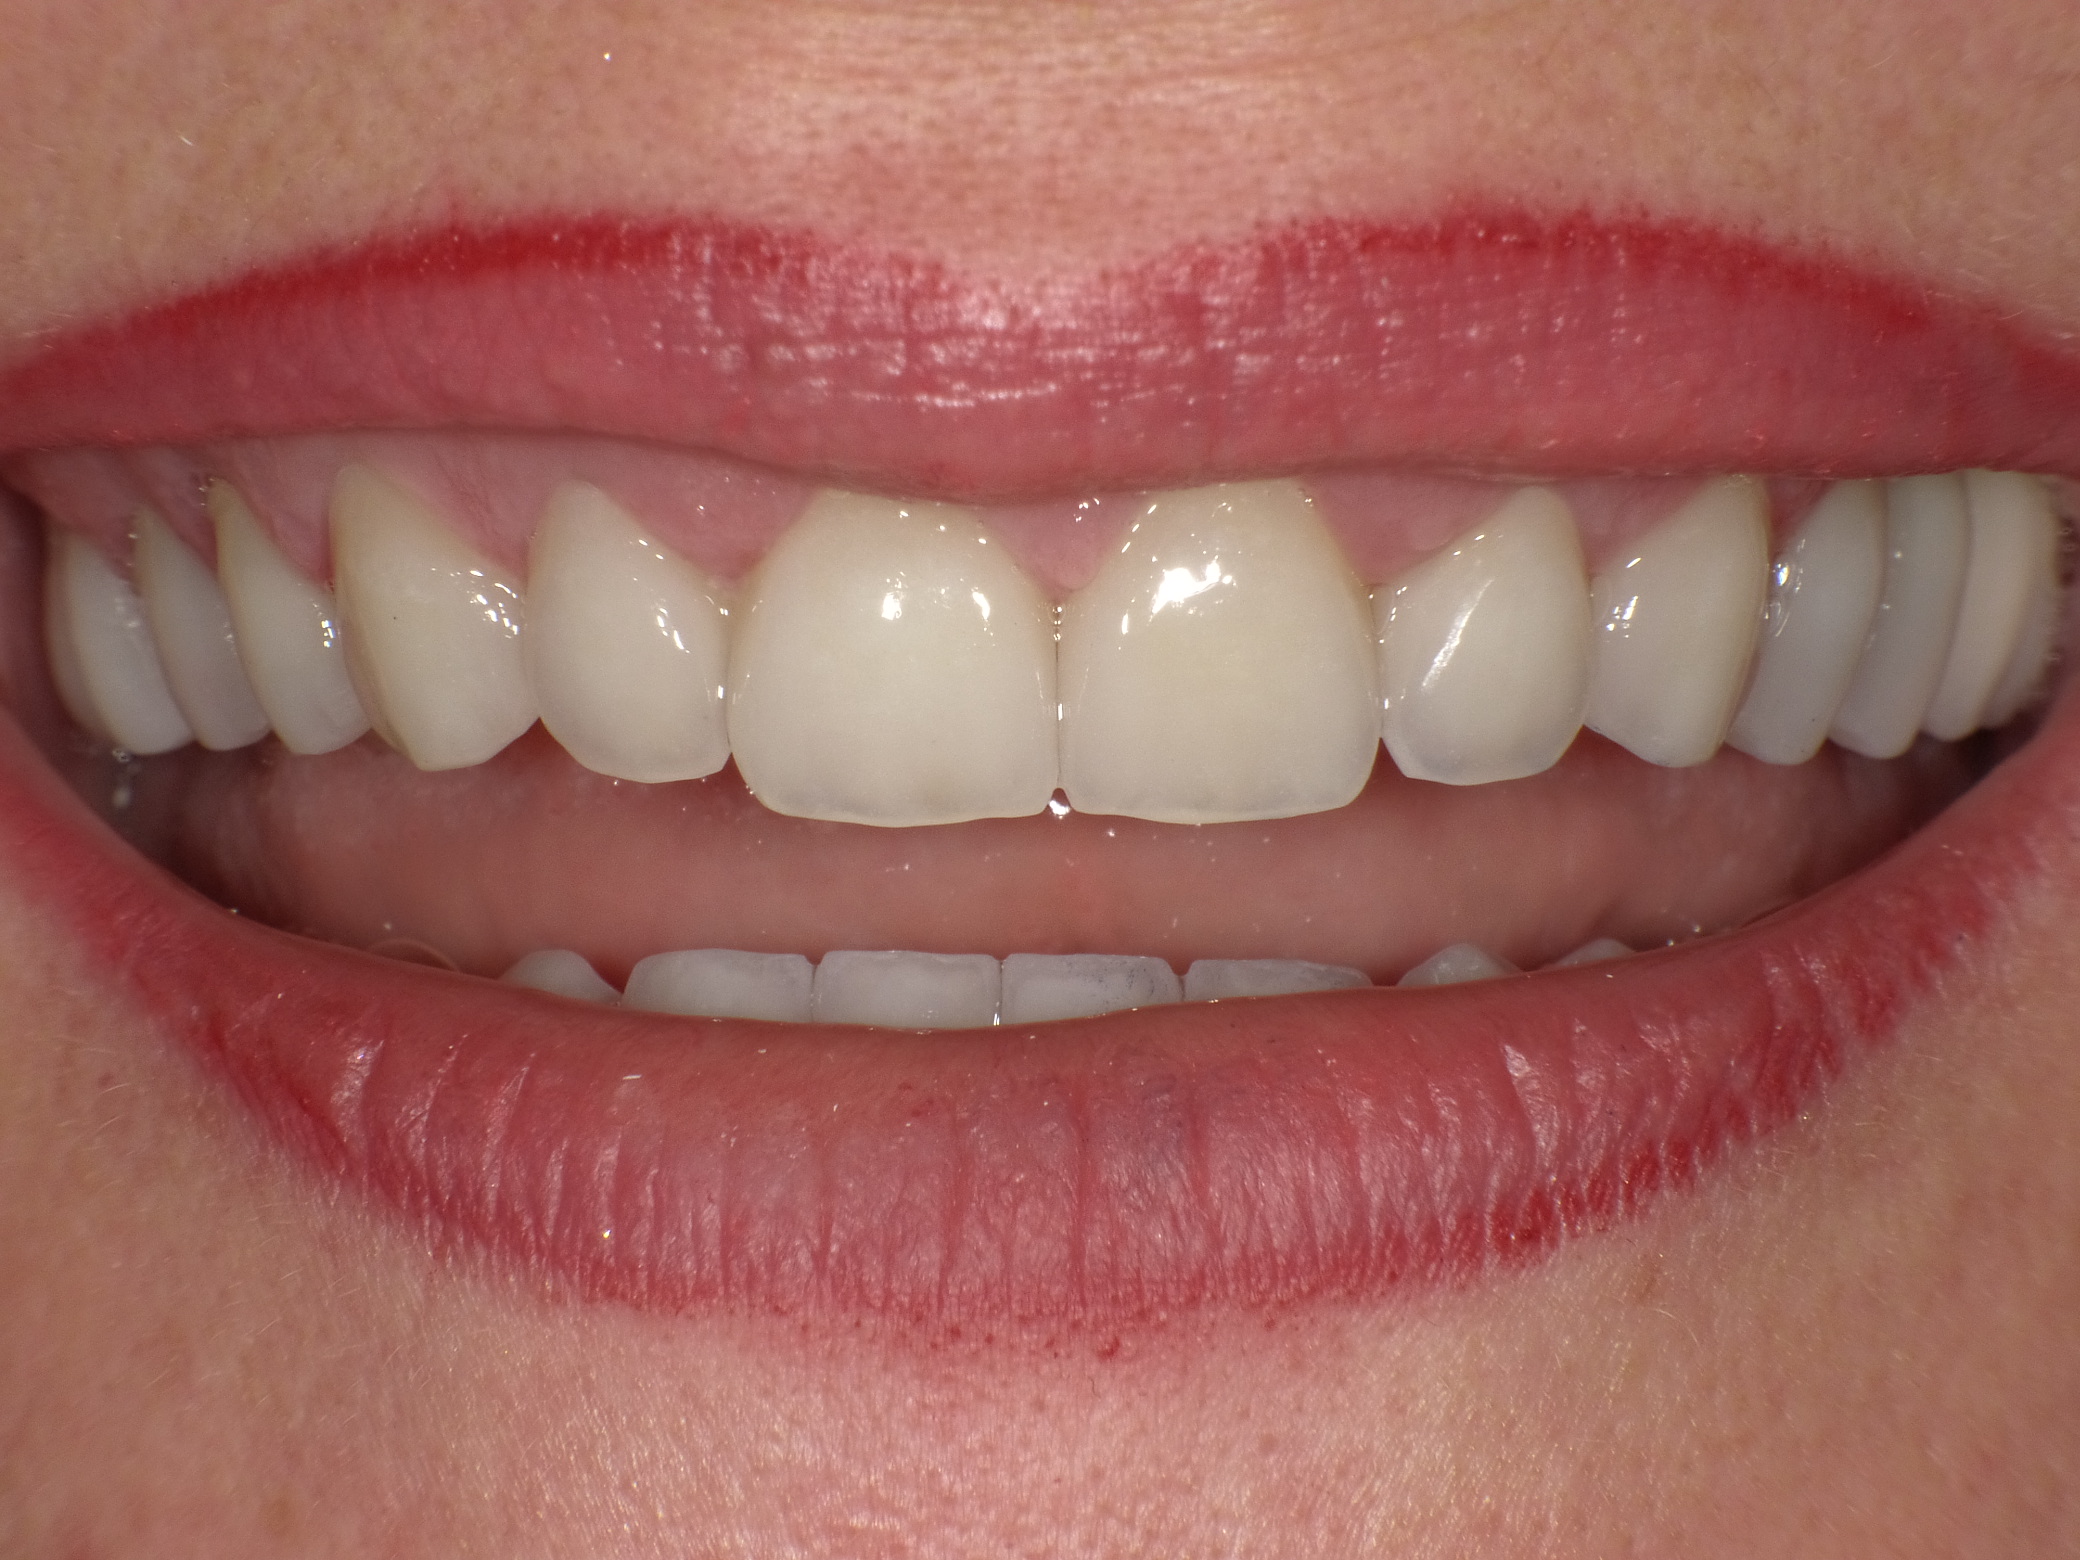

Ergebnis nach nur 2 Langzeit-Behandlungsterminen mit vollkeramischen Veneers und Kronen

Nachher: Ergebnis nach nur 2 Langzeit-Behandlungsterminen mit vollkeramischen Veneers und Kronen

Patientin mit dem Wunsch nach ästhetischer Optimierung der Gesamtsituation

Vorher: Patientin mit dem Wunsch nach ästhetischer Optimierung der Gesamtsituation